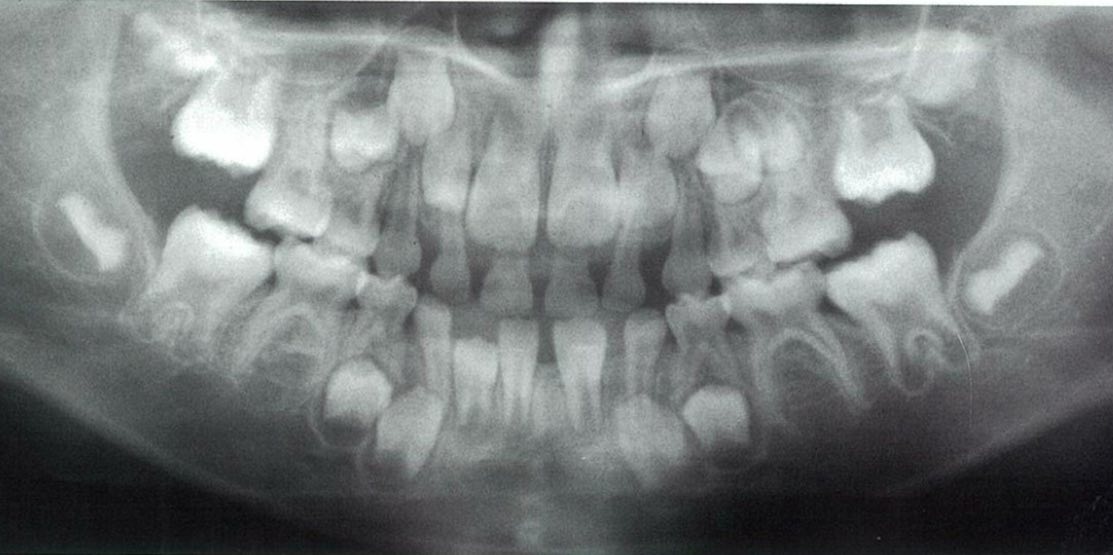

6歳の男児。定期診査を希望して来院した。来院時のエックス線写真を別に示す。

スクリーンショット 2017 01 31 11 14 40

a Hellmanの歯齢はⅢA期である。

b 下顎切歯が1歯不足している。

c 犬歯の歯冠の位置は正常である。

d 下顎第二小臼歯が1歯不足している。

e 第一大臼歯の歯根形成は遅延している 。

正答 b,c

a ヘルマンの歯齢が悩みます。6も1も萠出途中だし、どっちだったっけ、ⅡCだったかⅢAだったか。。。そもそも、ⅡCとⅢAの明確な違いってなんだっけ。。。

x線の所見は本当に見慣れていないときついです。「c 犬歯の歯冠の位置は正常である。」って自身持って選べる学生は少ないと思います。臨床でがっつり症例こなしたりすると自然に身につくようなもんでしょうけど、学生で教科書にのっている数枚のレントゲンしか見ていない状態だときついものがあります。

以上を踏まえて問題のレントゲンを見てみると、、、上下6が萌出途中で、噛み合っていませんよね!ということで、これはⅢAになれていないので、ⅡCだと一発で判断することができます!

実は、国家試験の正答は間違っています。選択肢の「d 下顎第二小臼歯が1歯不足している。」が、誤答肢になっていますが、これは実は正しいです。パノラマをよく見てみると右下5の歯胚が薄くですが、でき初めています。この感じだと左下5も今後でてくる可能性は十分にあります。

御存知の通り、先天欠如の多い歯種は「8」「5」「2」ですね。それぞれ、「大臼歯」「小臼歯」「切歯」でもっとも遠心にある歯は退化傾向で、先天欠如が多いことで知られています。この問題のパノラマも「5」がその傾向にあり、下顎では歯胚の形成がすごく遅れており右下5のみ確認できます。上顎では左上5が正常に発生していますが、やはり右上5の歯胚は確認できません。

よって、本当はこの「d 下顎第二小臼歯が1歯不足している。」は微妙な選択肢で、最近の感じだと削除かこの選択肢も丸になる流れになると思います。クレームがついてもきちんとした反論はできないかと思わます。(一応、この内容は、大学の小児歯科の先生に確認とれていますし、ANSWERでは画像所見の欄にのみ指摘されています。)